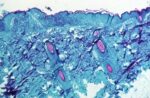

Monkeypox: OMS reporta menos casos mas pede aos países para não baixarem a guarda

O diretor geral da Organização Mundial da Saúde, Tedros Adhanom Ghebreyesus, destacou que o número de novos casos de monkeypox … Continue a ler Monkeypox: OMS reporta menos casos mas pede aos países para não baixarem a guarda